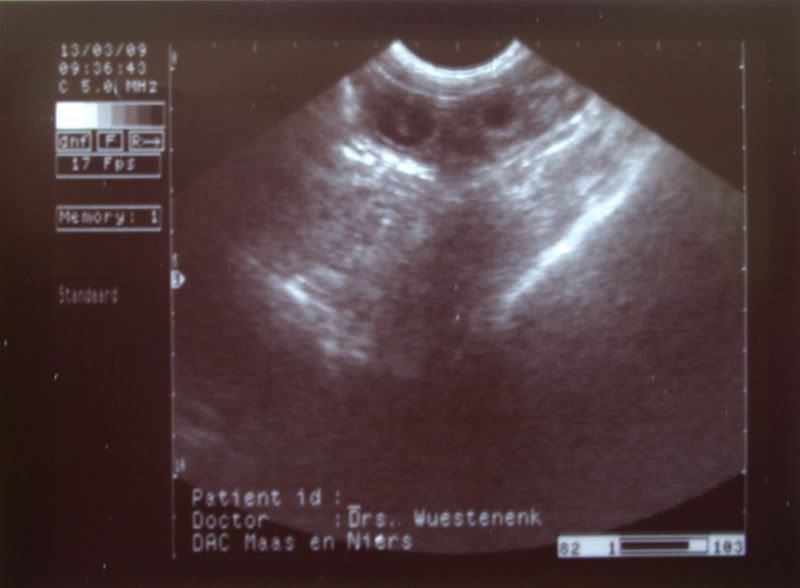

Ben vandaag met Aika voor de echo geweest en ja hoor, ze is drachtig.

Ik had het vermoeden al, maar het is toch echt wel fijn als het ook bevestigd is.

We hebben verschillende vruchtjes gezien, maar echt tellen was moeilijk.

Ben zo blij